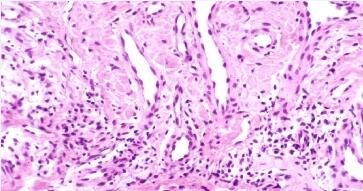

艾滋病的皮肤损害-丘疹性皮损:典型皮损位于头、颈和躯干上部,为直径主一3mm互不融合的丘疹.正常皮色。病程较长,常伴瘙痒。组织病理显示血管周围有单核*为主的慢性炎性*浸润。